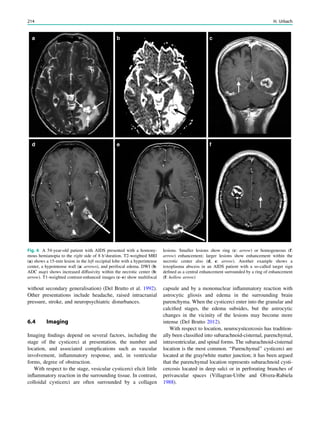

Fig. 2 Epileptogenic lesion and symptomatogenic zone. A 40-year-

old woman suffered from complex focal seizures with a fearful face

and body rocking. The symptoms thus pointed to the mesial frontal

lobe as the origin. MRI shows right-sided hippocampal sclerosis

(a, arrow). Simultaneous video and EEG recordings from interhemi-

spheric (c) and convexity strip and intrahippocampal depth (b) elec-

trodes show seizures starting in the right hippocampus (d, arrow).

Clinical symptoms start around 1 s afterwards (d, asterisk)